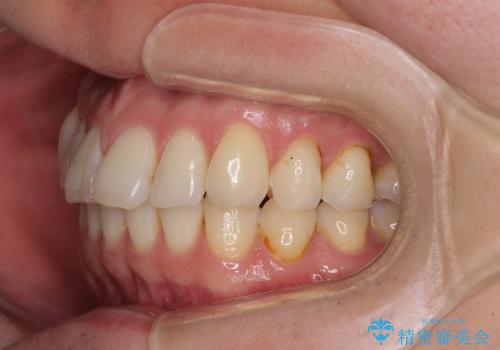

- 以前矯正治療を行ったものの、思い通りの仕上がりではなく、更には後戻りが気になってきたとのことで来院された患者様です。

上顎右側の第一小臼歯が動きにくい歯であり、以前矯正治療を行った際に傾斜した位置のまま終了したことと、それに伴い後戻りで歯列が波打っているようになっていることを大変気にしていらっしゃいました。